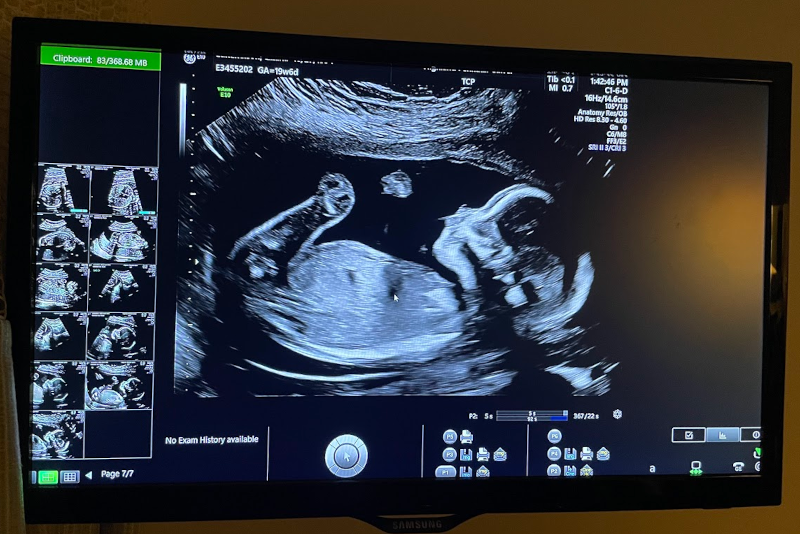

We walked into the ultrasound room, filled with a mixture of excitement and apprhension, hoping that our child would be viable. Lili lay down, and the technician got to work. “The jelly is warm!” Lili commented, pleasantly surprised that it wasn’t freezing cold. The first image of our child was projected on the screen before us, and we couldn’t stop smiling. One by one the technician catalogued the baby’s parts, their humeri, femurs, the valves of the heart, the fingers, the toes, the brain, the spine, and more–we got to see it all. Our hope bloomed and meshed with reality. The baby was fine. And wiggled a lot. It was positively magical to watch.